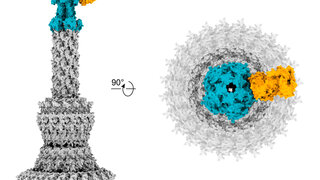

Eine Zahnfeile, die rotiert und schwingtPiezokeramik verkürzt Wurzelbehandlungen Forschende des Fraunhofer-Instituts für Keramische Technologien und Systeme (IKTS) in Dresden haben ein Feileninstrument konstruiert, das die Arbeit des Zahnarztes erleichtert und die Behandlungszeit verkürzt. 03.11.2023 Zahnmedizin